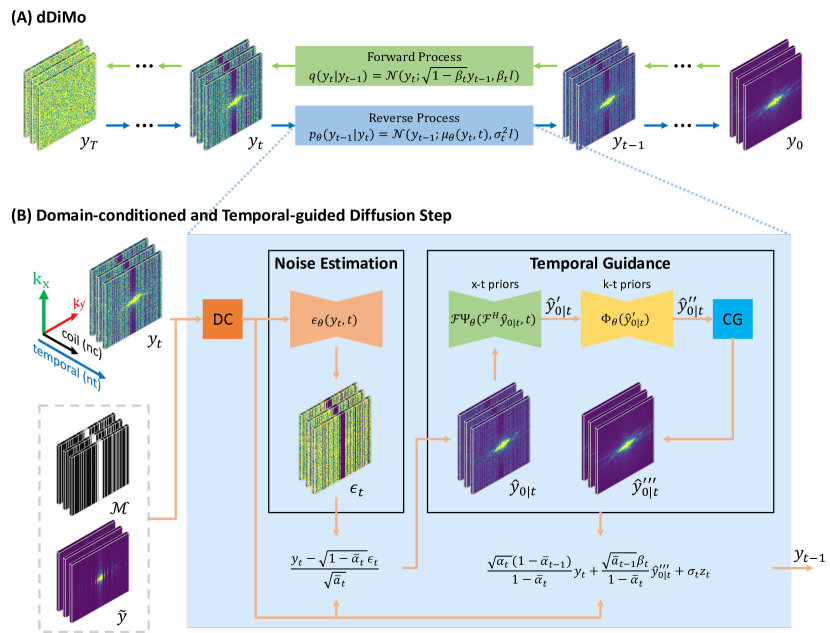

Inherited from the original DiMo method, the dDiMo framework features a forward diffusion process that introduces noise into k-space, followed by a reverse diffusion process that removes the noise to recover data. Unlike the original DiMo, which reconstructs static images, dDiMo incorporates additional temporal information from time-resolved dimensions, allowing it to capture dynamic features and enhance image reconstruction for dynamic MRI data. An illustrative diagram of the proposed dDiMo framework is presented in Figure 1. This new framework includes several key components designed to adapt to the reconstruction of dynamic image data: (1) A 3D CNN-based noise estimation network that characterizes spatial features within frames and temporal dynamics across frames, leveraging temporal coherence to learn denoising priors aware of temporal changes. (2) A 3D CNN-based - network that captures temporal dynamics in the spatiotemporal image domain from intermediate denoised results, guiding the diffusion process toward better temporal alignment. (3) A 3D CNN-based - network that enforces MRI physics constraints through data self-consistency learning within the ACS region of - space, refining the denoising process and ensuring consistency within k-space. (4) A nonlinear CG module that iteratively refines the reverse diffusion steps, maintaining adherence to physical constraints and enhancing robustness. Further details about each component will be provided in the following sections.

2.2.1 Diffusion modeling for dynamic data

Forward Diffusion: The forward diffusion process in dDiMo is modeled as a Markov chain that progressively adds Gaussian noise to a dynamic sequence of fully sampled multi-coil k-space data, denoted as . This dynamic sequence includes multiple adjacent time frames, and the process is conditioned on the acquired measurements , which also span multiple time frames, along with the corresponding undersampling mask . The forward diffusion process transforms the initial distribution into a sequence of increasingly noisy samples, which can be mathematically represented as:

Unlike static image data, this diffusion modeling processes several adjacent time frames at the same time, allowing it to utilize temporal information across frames during the training of the denoising network. This approach helps maintain better temporal alignment throughout the reconstruction. By taking inter-frame relationships into account, the dynamics of the forward diffusion process are influenced by both temporal and spatial factors. This enables the model to capture the inherent spatial structure and the temporal evolution within the dynamic series effectively.

Reverse Diffusion: In the reverse diffusion process, the multi-coil dynamic k-space series is generated by initializing from random Gaussian noise and progressively removing the estimated noise over steps. This process can be formalized as:

where denotes the noise prediction model using a CNN, for example, a U-Net [41, 42]. To capture the spatiotemporal features of the dynamic data, we applied 3D convolutional layers (i.e., 2D spatial + 1D temporal) in a 3D U-Net (Supporting Information Figure 6) to extract both intra-frame and inter-frame information, enabling the model to exploit the underlying spatial-temporal coherence of the data for more effective noise removal. Additionally, like DiMo [47], data consistency (DC) is incorporated into estimating , where a linear combination of partially scanned data is added to to ensure data fidelity.

where represents the predicted noise at step , denotes a random variable sampled from the normal distribution. The can be obtained by repeating the reverse step times recursively. However, this standard diffusion process has not incorporated explicit modeling in the - and - domains, which can be further utilized to characterize temporal features, as described in the following sessions.

2.2.2 - priors for spatiotemporal learning

Like conventional reconstruction to leverage regularization in the - domain, we further investigated the characterization of temporal image features by explicitly learning from the data in the - domain. This is achieved using a 3D CNN to learn the associated - priors based on the intermediate denoised image sequences. Although it seems intuitive to directly learn these features from the intermediate results in Eq. (14) during the reverse process, applying - prior learning directly to can lead to suboptimal performance. This is primarily due to the substantial noise present in the early stages of the reverse process, which can obscure the true temporal features. To address this challenge, we propose a strategy for learning - priors based on “clean” data. Inspired by previous work in diffusion [48], we can isolate the underlying “clean” data from the noisy data using the following approach:

2.2.3 - priors for data self-consistency

Shift-invariant k-space correlations from fully-sampled auto-calibration signal (ACS) regions have been widely used for k-space interpolation and as regularization priors in MRI reconstruction [3, 22, 31]. In dynamic imaging, similar - patterns can be extracted from ACS data across consecutive time frames [49, 50]. Inspired by the work from scan-specific neural networks for k-space interpolation[22] and our previous k-space implementation [50, 31], we utilize a 3D CNN with four convolutional layers, each with a kernel size of 333, as shown in Figure 2, to capture - correlations through a self-consistency learning mechanism during the training phase. This process involves feeding ACS data from multiple time frames into the network, enabling it to learn the underlying - patterns by predicting the input data itself as accurately as possible, expressed mathematically as:

2.2.4 Nonlinear conjugate gradient layer

Followed by the - and - feature characterization through CNNs, a layer implementing the iterative nonlinear CG is applied to refine the result in each of the reverse diffusion steps. This iterative refinement using CG enhances the robustness of the reverse diffusion process to noise perturbations. It also complements the automatic learning process by reinforcing well-known image features, such as temporal sparsity, into the diffusion process. The CG layer is formulated as:

Once the temporal-guided “clean” data has been obtained through - and - regularization and non-linear CG refinement, it can be converted back into its original state at the diffusion step as:

The final can be obtained by repeating the reverse diffusion step times recursively following Eq.(21).